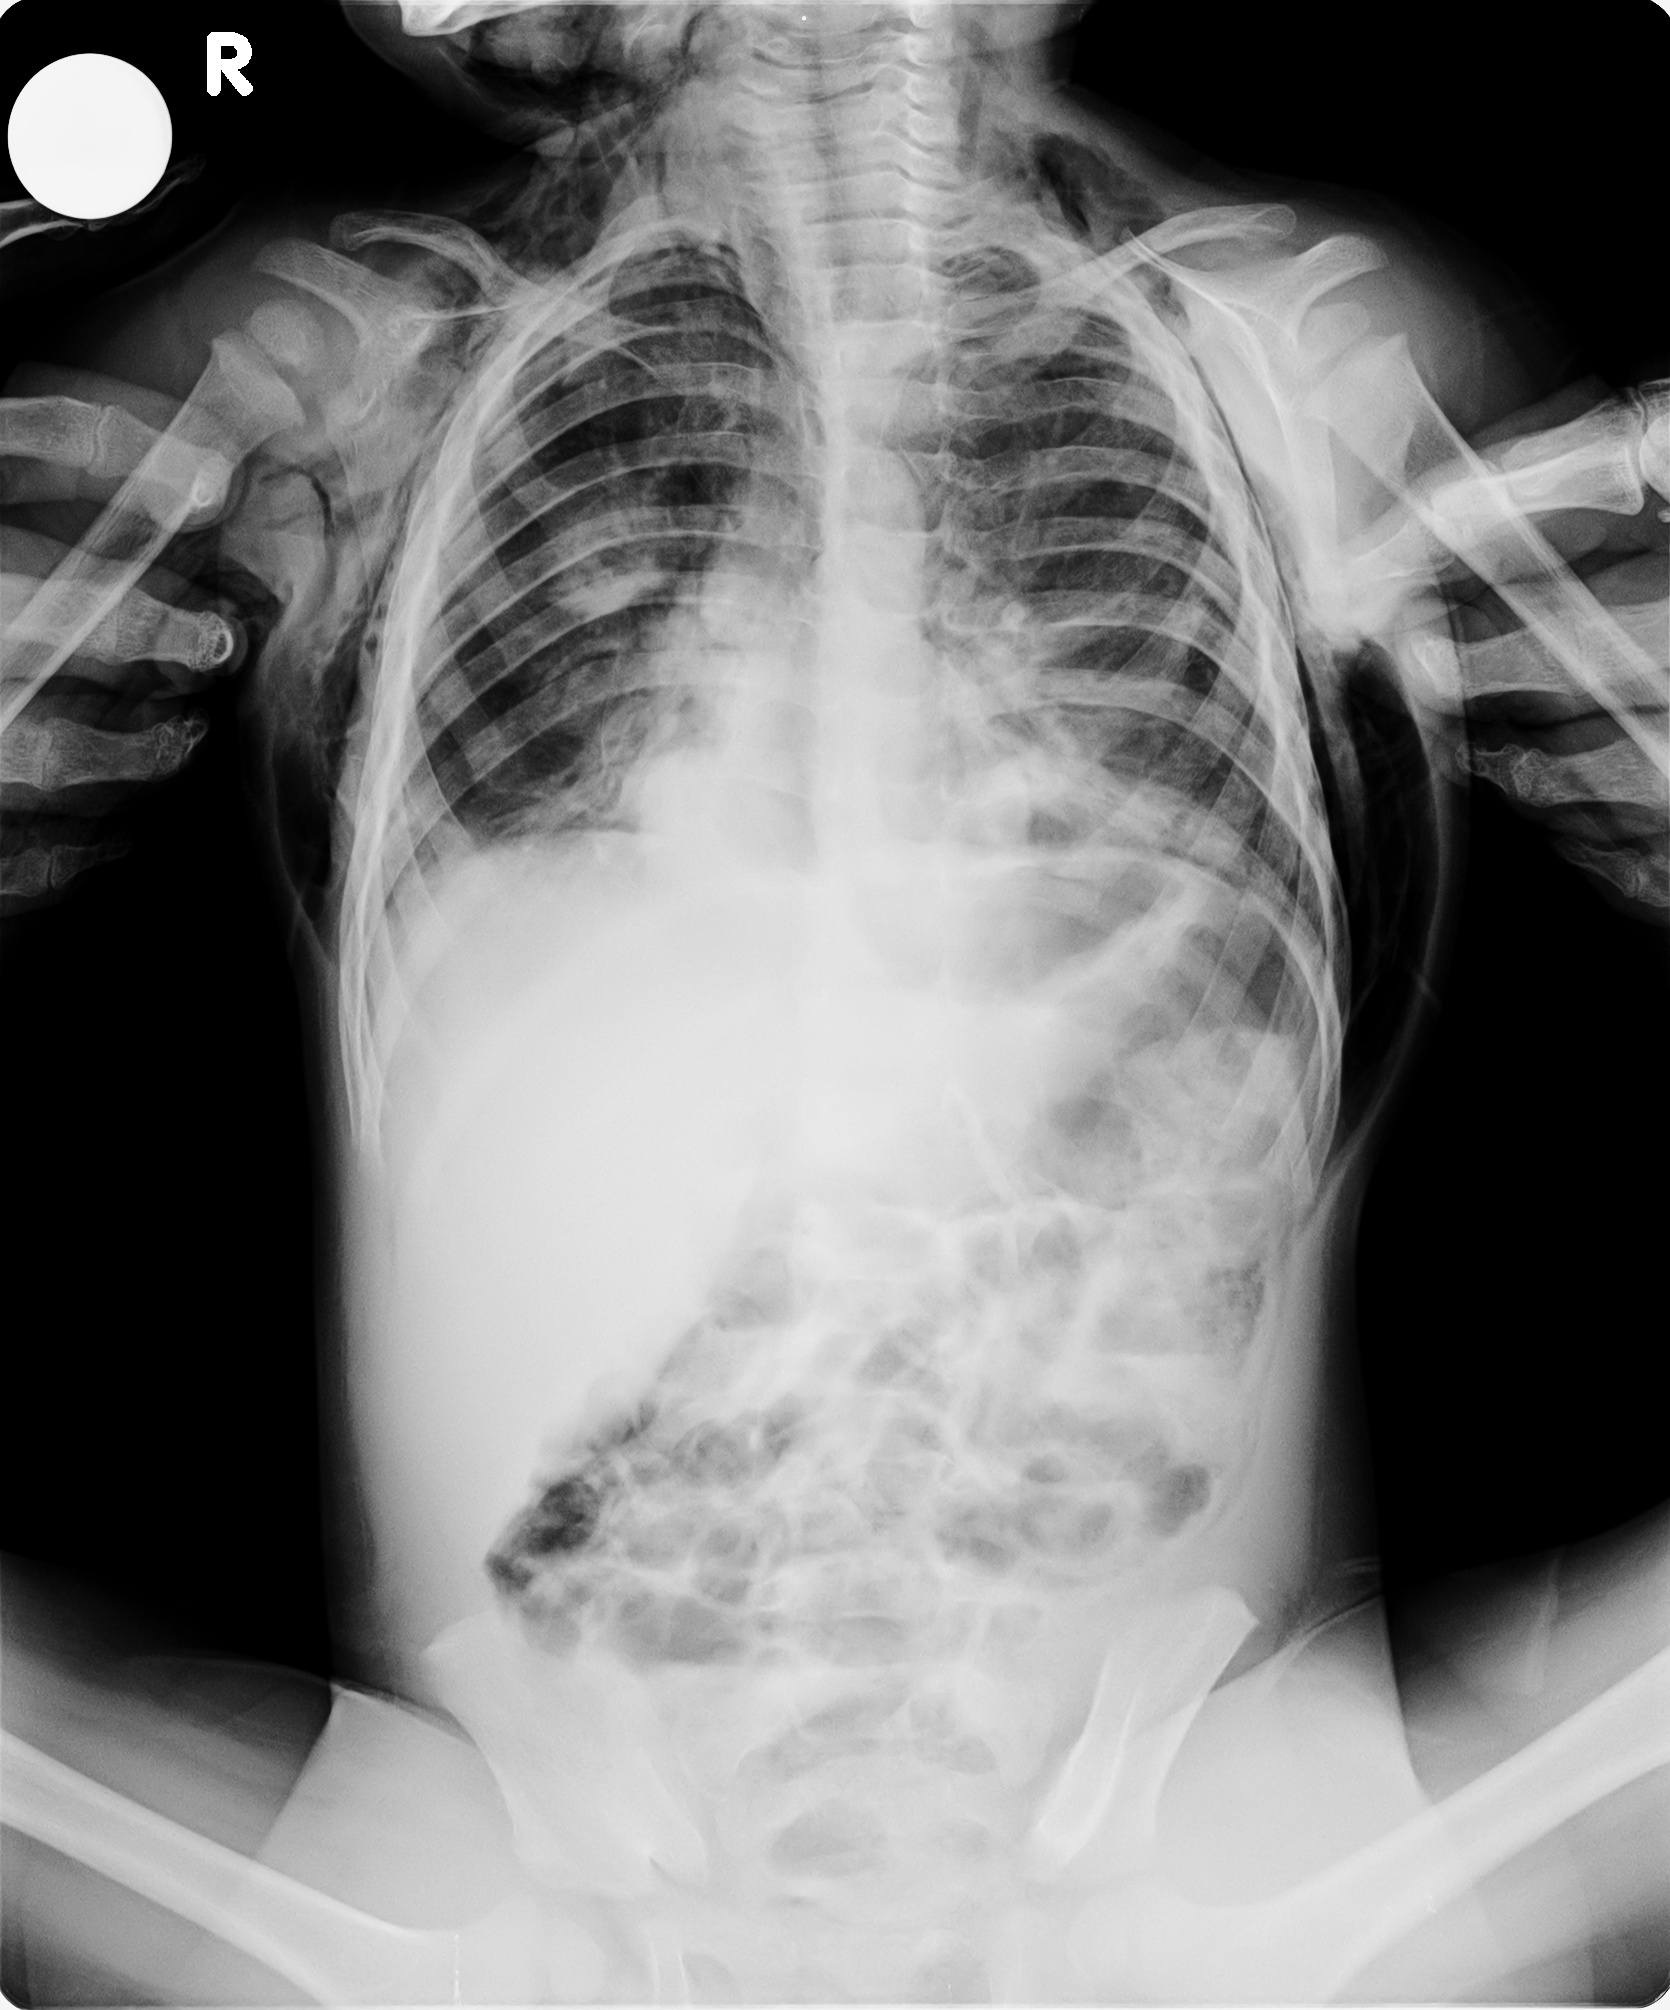

Unexpected Presentation of Tracheoesophageal Fistula During Intubation

Unexpected Presentation of Tracheoesophageal Fistula During Intubation Baby Rattly Chest After Cold Symptoms of bronchitis can be similar to a cold or flu. A chest infection is worse than a heavy cold and is extremely common, affecting about a third of babies in their first year. Check if you have a chest infection. Without treatment, bronchitis can become pneumonia. The rattling in your chest. Bronchitis affects the bronchial tubes, while pneumonia affects. Baby Rattly Chest After Cold.